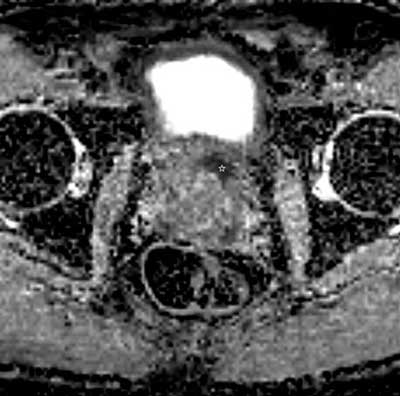

Figure 2

Axial ADC map of DWI in the same patient and at the same level as Figure 1. The lesion shows very low ADC value (white star) with corresponding very high signal intensity on the high-b-value images (not presented), which is suggestive of a high-grade prostate cancer. In the radiology report this lesion was scored PI-RADS 4, indicating that the likelihood of a clinically significant prostate cancer is high.